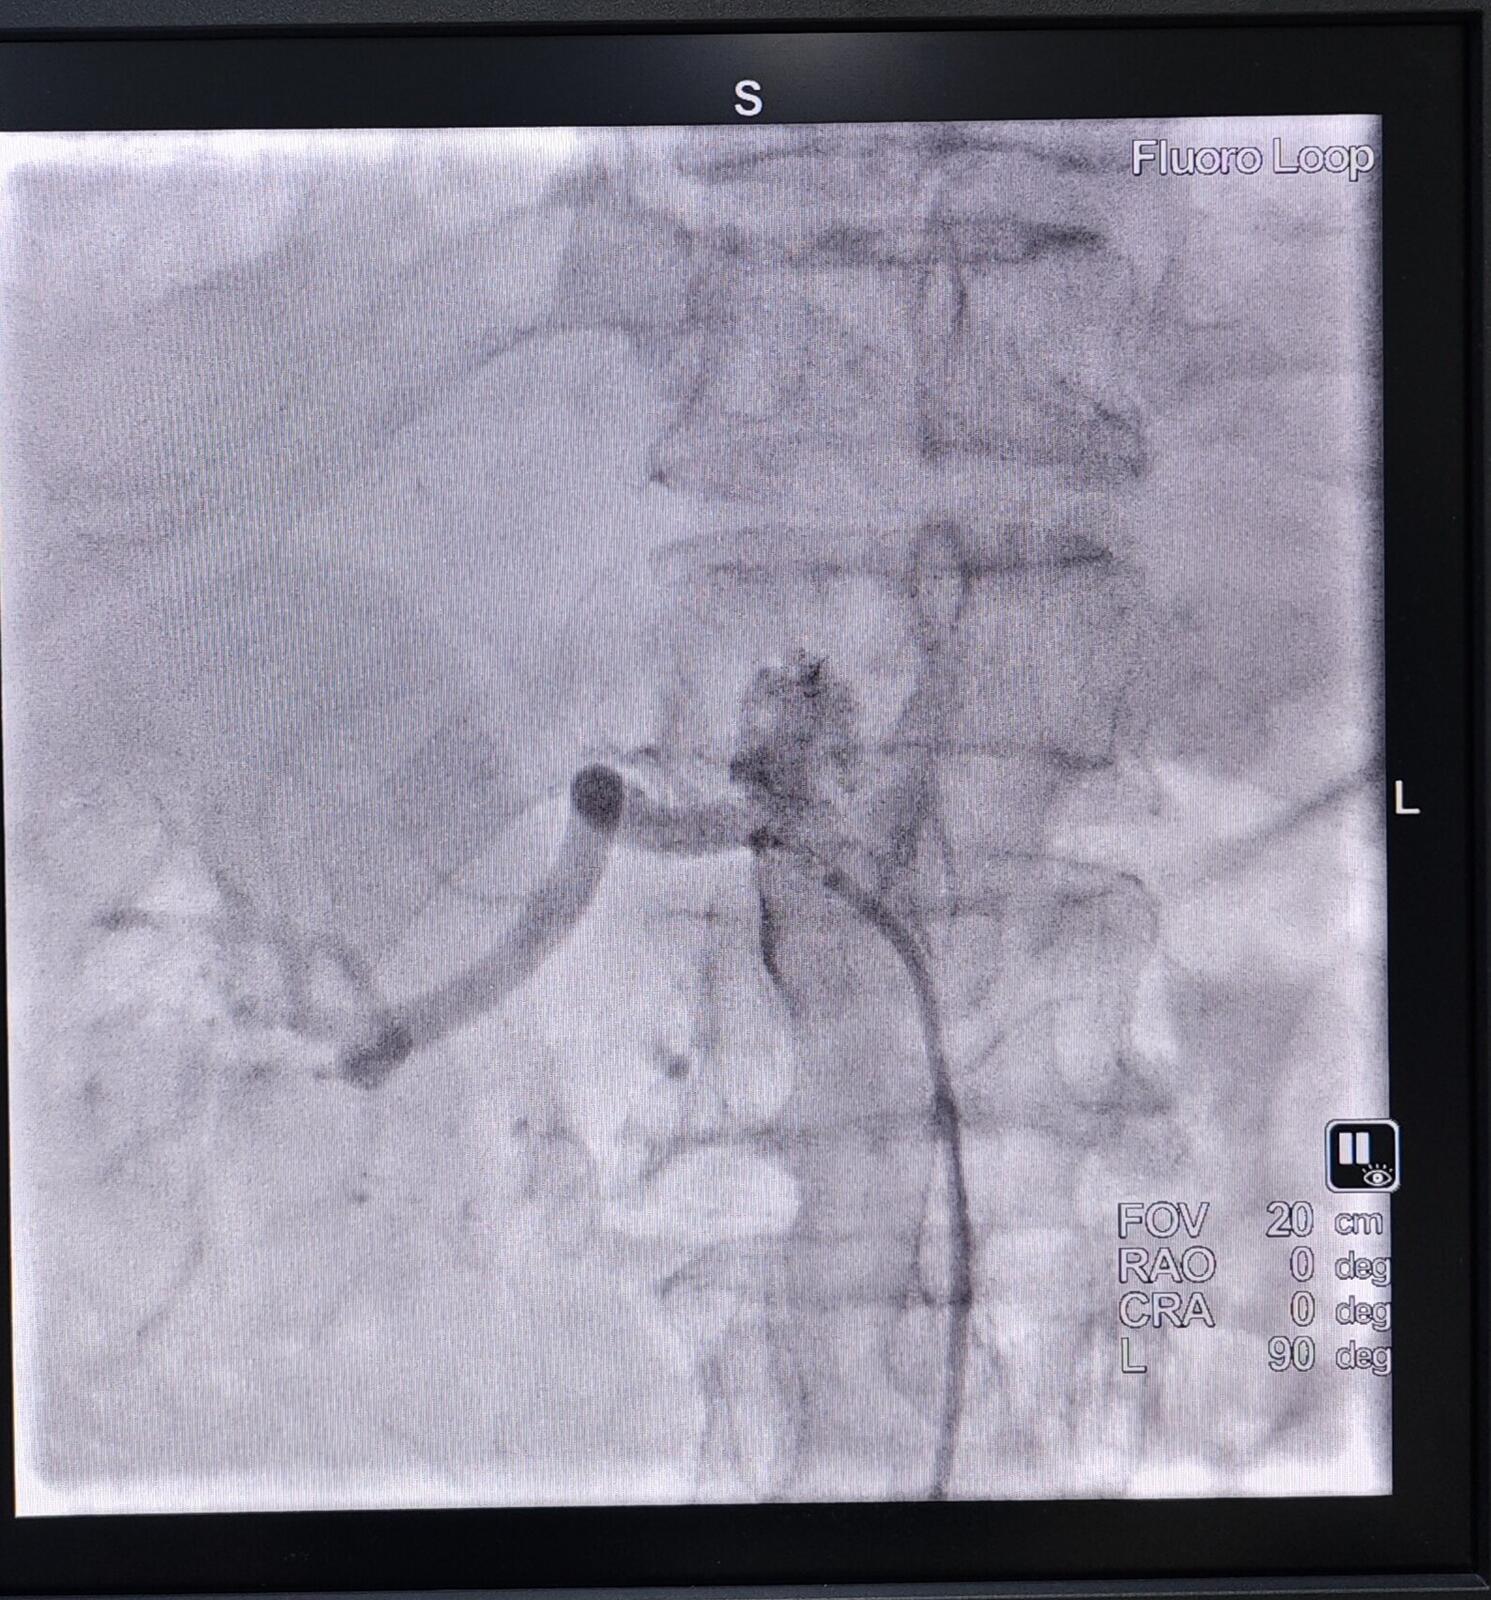

患者男,74岁,在心内科应用包括利尿剂在内的3种降压药后收缩压仍无法控制到190mmHg以下。入院肌酐193.3umol/L、尿素16.65mmol/L。CTA提示左肾萎缩无动脉显性,右肾动脉狭窄超过95%。临床上肾动脉狭窄引发高血压患者肾衰的患者很多,但是能拖到一侧肾脏完全萎缩坏死,一侧肾动脉狭窄超过95%委实少见。该患继续内科保守治疗血压控制差、肾功持续衰竭,怎么办?

→_→肾动脉介入治疗过程:取仰卧位,常规消毒、铺无菌巾,局麻后穿刺股动脉并置入血管鞘。于患者的第1腰椎处放置猪尾导管行腹主动脉造影明确患者的肾动脉开口以及狭窄的情况。然后通过Cobra导管,进而选择肾动脉造影,从而使狭窄的程度、狭窄的部位、长度以及狭窄段两端正常RA的管腔直径得以明确。利用专用导丝和导管将选好的球囊和支架送到发生病变的位置,球囊扩张后准确释放支架。